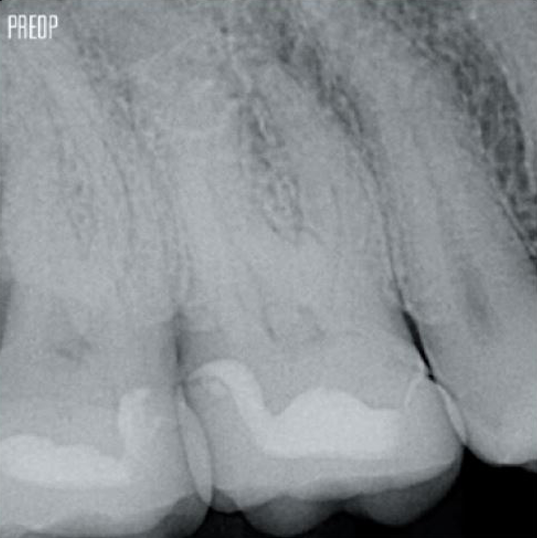

Fotos mit freundlicher Genehmigung von Dr. Ahmed Salman

Mehr erhaltenes Dentin. Angemessene Formgebung, Spülung und Obturation gewährleistet.